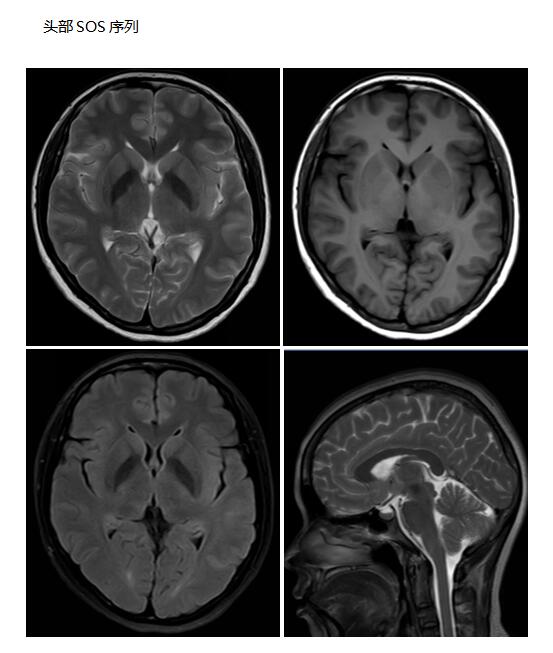

特有的运动伪影消除技术,即使患者在扫描时有不自主运动(如帕金森综合症),也可以获得令人满意的图像,为临床的诊断及治疗提供有力的影像学资料;

中枢神经系统应用

可应用于颅内外肿瘤性病变,脑卒中病变、血管性病变、感染性病变、外伤性病变,脑白质病变,先天性发育异常、退行性病变等中枢神经系统疾病检查,尤其是脊柱及脊髓病变,同时可以全脊柱成像,整个脊柱及脊髓病变一览无余,无处藏身。